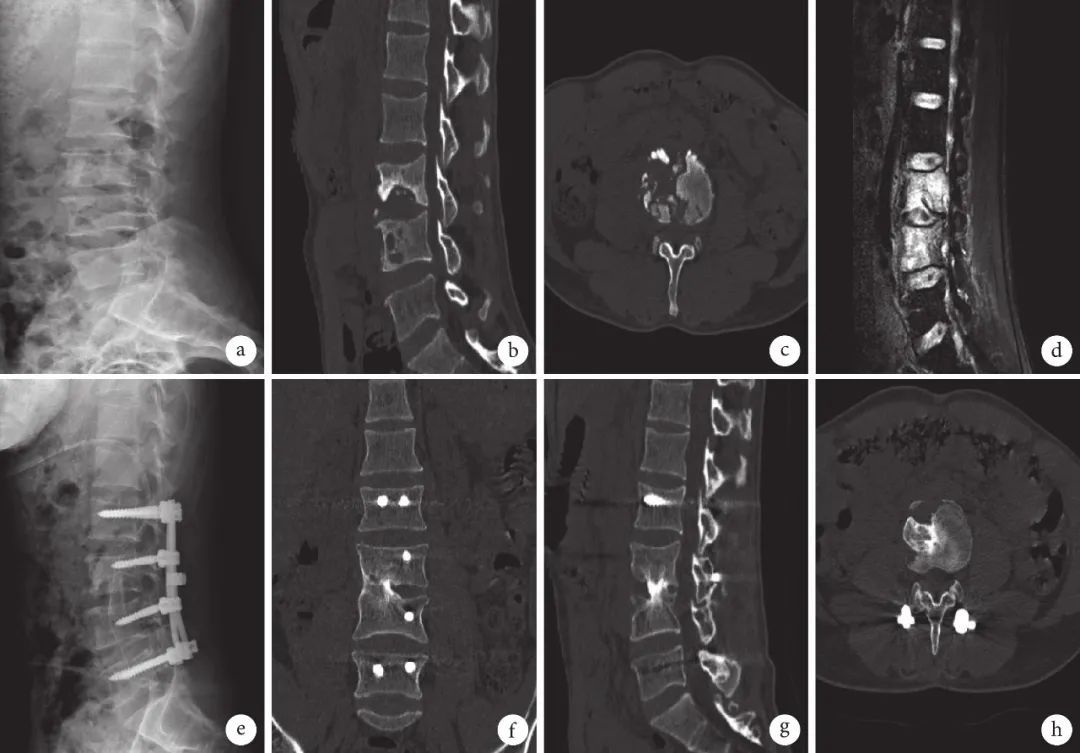

图 3 自体髂骨组患者,男,62岁,L3、4椎体结核 a. 术前X线片示椎体骨密度不均;b~d. 术前CT及MRI示椎体多发骨质破坏伴右侧椎旁脓肿形成;e. 术后1 个月X线片示椎间融合及内固定物位置良好;f~h. 术后6个月CT及MRI示自体髂骨植骨块局部骨性融合、各椎间隙存在